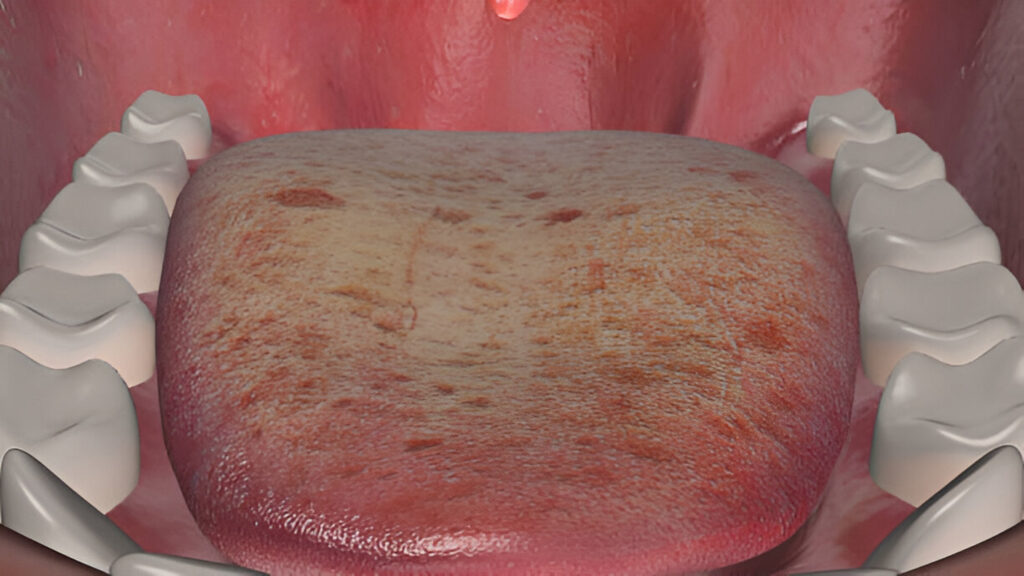

Oral Infection Treatment

Untreated oral infections can lead to detrimental dental conditions and eventually illnesses. Our center specializes in the diagnosis and treatment of these infections making sure that the treatment is comfortable and it lasts for a long time.

What is Oral Infection Treatment?

Oral infection treatment involves diagnosing and addressing infections in the mouth, such as abscesses, gum infections, or tooth-related bacterial issues. At Al Rayashi Dental Center, we use advanced diagnostics and effective care plans to relieve pain, stop the spread of infection, and restore oral health.